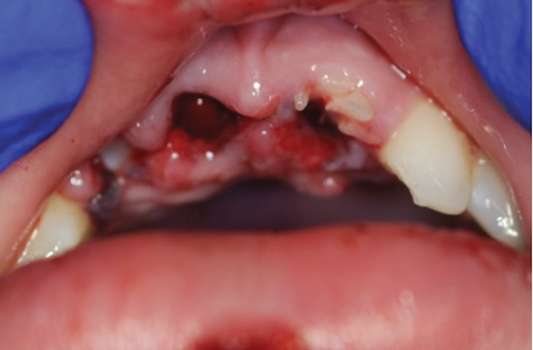

Orofacial injuries from ENDS explosions have been documented with low incidence.37 These incidents tend to occur due to excessive heating of the unit's internal lithium-ion battery. Injuries can include tooth fractures, dentoalveolar fractures, hematoma formation, traumatic ulceration, burns, and palatal perforation (Figure 4 through Figure 7). Soft-tissue damage may require cosmetic and functional surgical reconstruction.

Fig 5. Oral injuries after e-cig explosion. Fig 4: Laceration of the lower lip vermillion with ecchymosis; Fig 5: Multiple lacerations with surrounding erythema on the upper labial mucosa; Fig 6: Hematoma of the lower labial mucosa with small midline ulceration; Fig 7: Resultant dental injuries included complete intrusion of tooth No. 7, avulsion of tooth No. 8, fracture of tooth No. 9 to the gingival margin, and incisal fracture of tooth No. 10. (Reprinted with permission from Journal of Oral and Maxillofacial Surgery.37 Copyright 2016, Elsevier)

Fig 6. Oral injuries after e-cig explosion. Fig 4: Laceration of the lower lip vermillion with ecchymosis; Fig 5: Multiple lacerations with surrounding erythema on the upper labial mucosa; Fig 6: Hematoma of the lower labial mucosa with small midline ulceration; Fig 7: Resultant dental injuries included complete intrusion of tooth No. 7, avulsion of tooth No. 8, fracture of tooth No. 9 to the gingival margin, and incisal fracture of tooth No. 10. (Reprinted with permission from Journal of Oral and Maxillofacial Surgery.37 Copyright 2016, Elsevier)